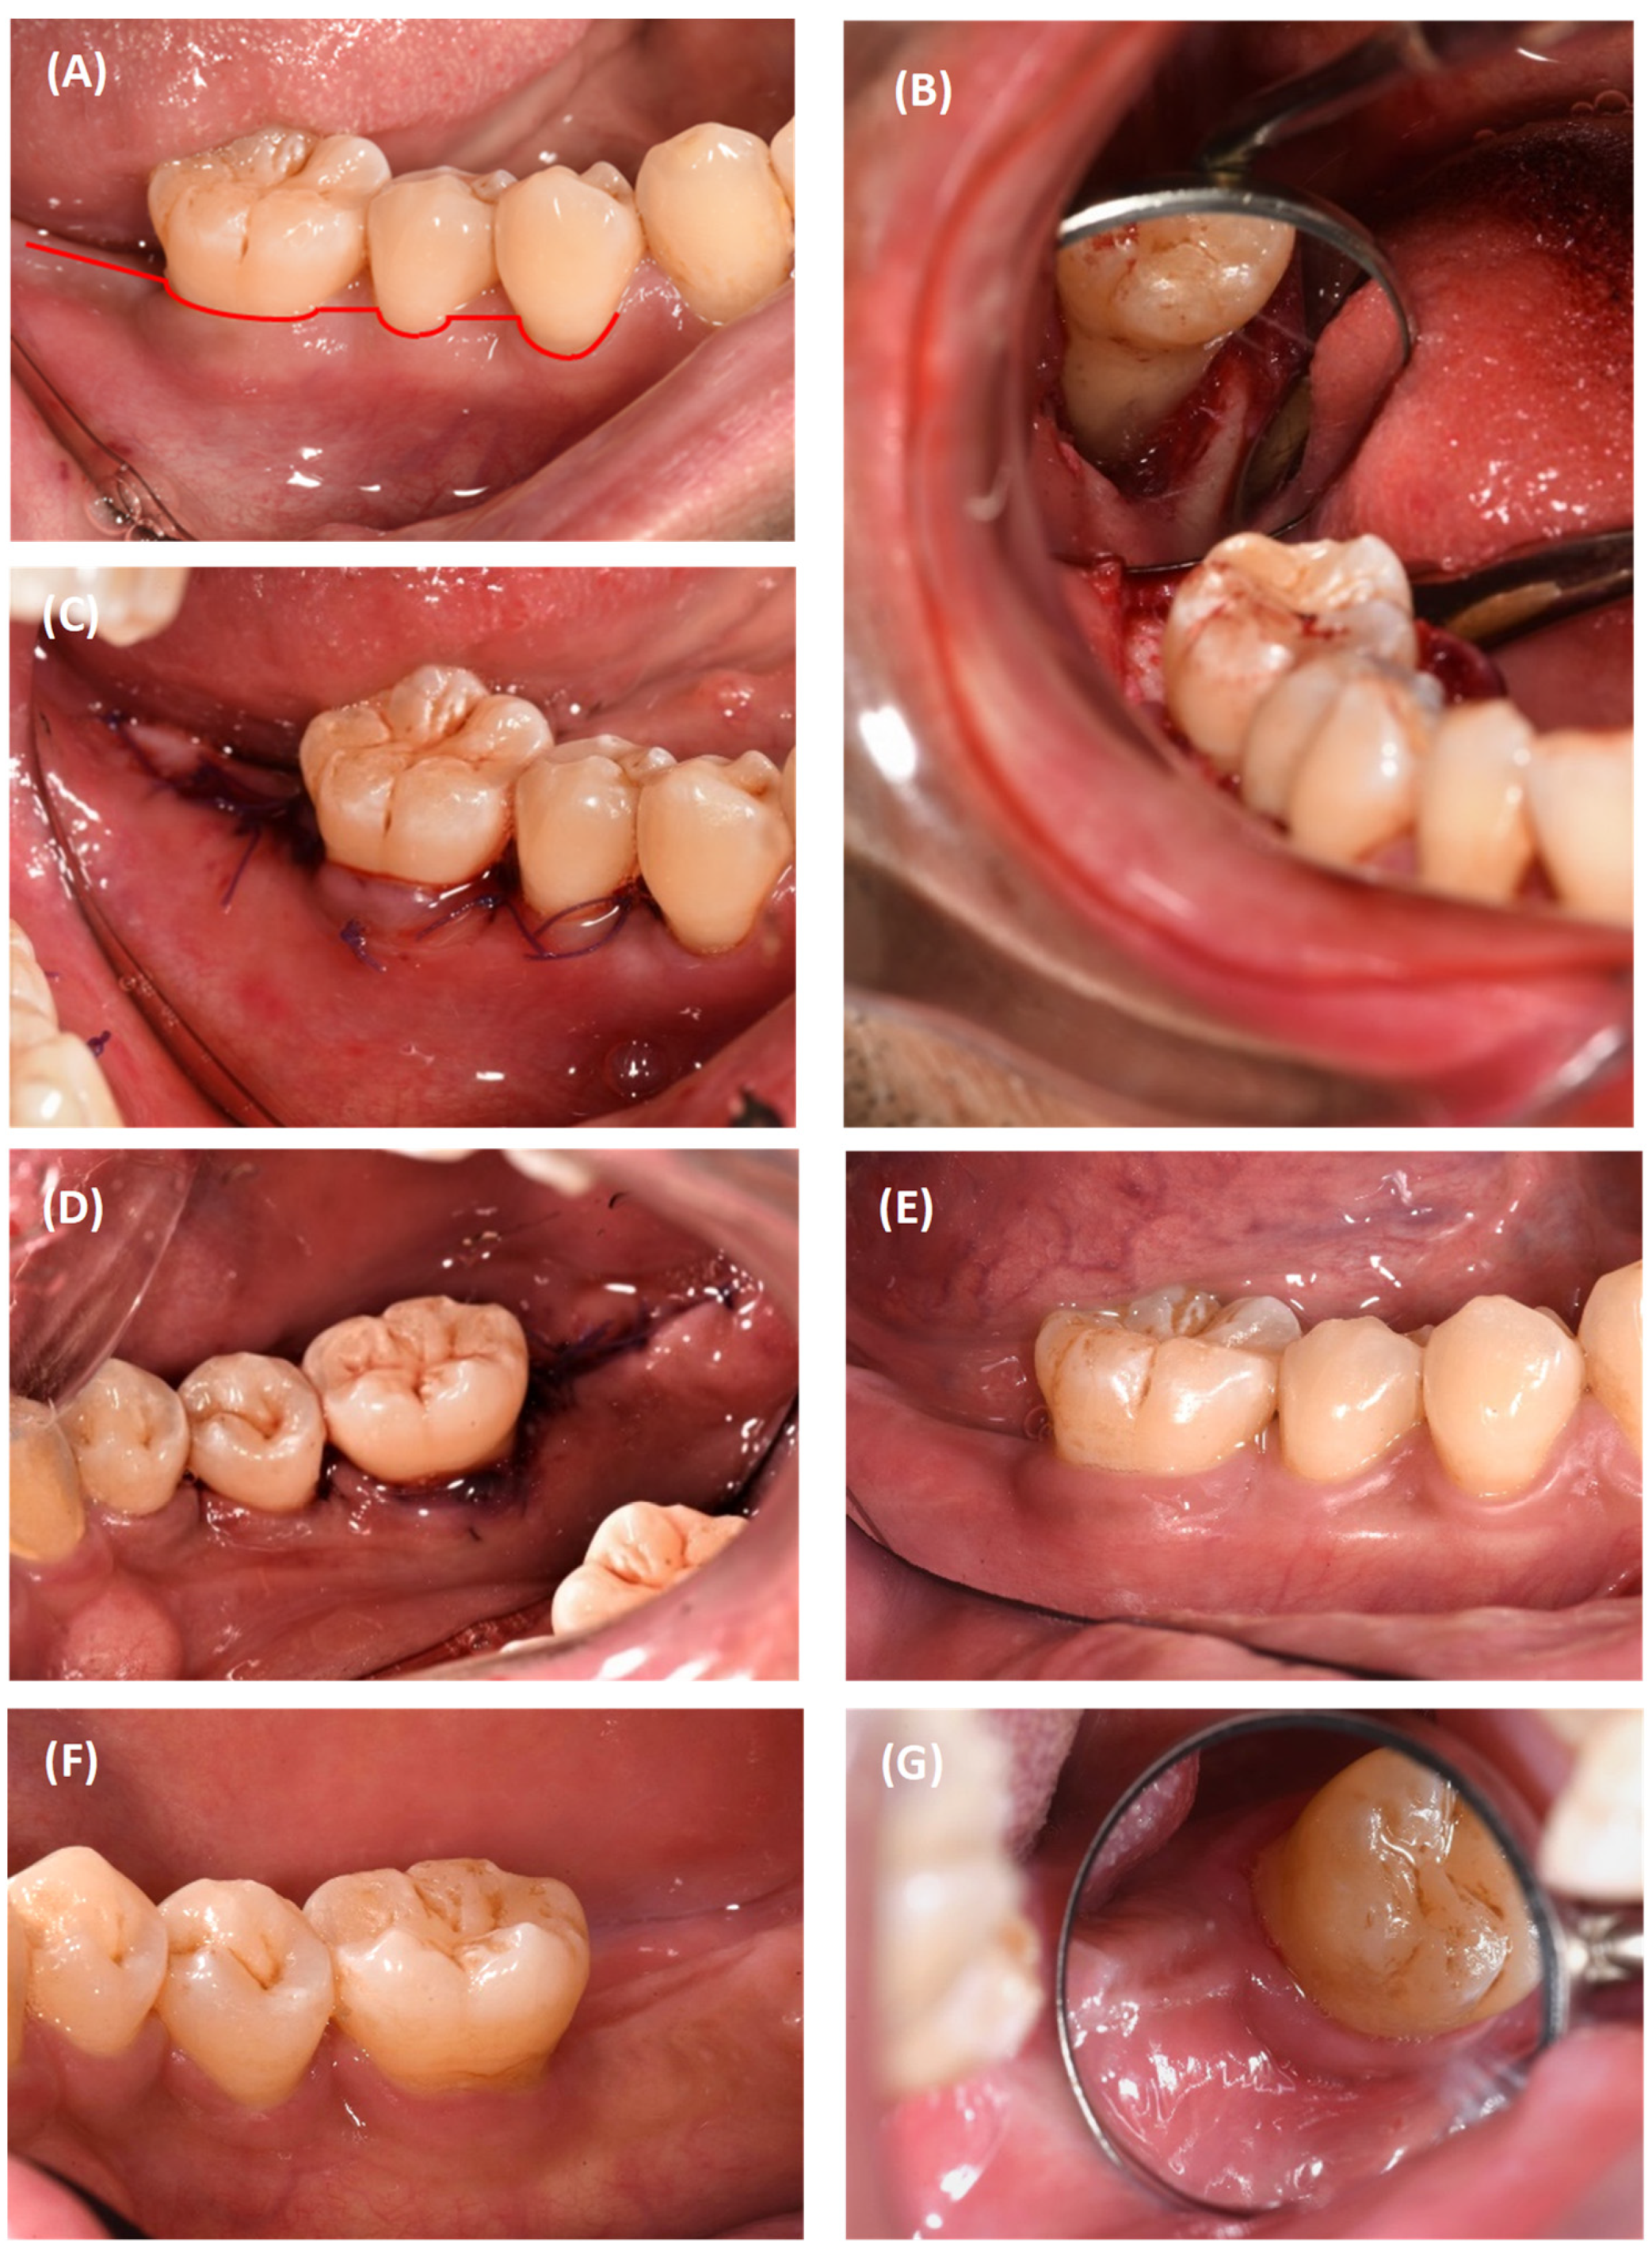

2.1. Case 1